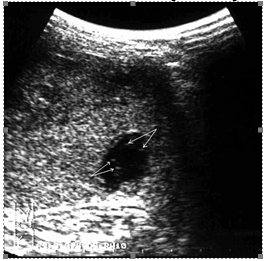

Прямым и наиболее постоянным (в течение острого периода травмы) эхографическим признаком подкапсульных разрывов селезенки с образованием внутриорганных гематом является наличие в паренхиме эхонегативной зоны (рис. 2, а, б). При гематомах, локализовавшихся в области полюсов селезенки или по ее диафрагмальной поверхности, эхонегативная зона имеет серповидную форму, повторявшую контур органа (рис. 2, в).

Рис. 2. Эхограмма подкапсульного разрыва селезенки: а – внутриорганная гематома; б – линейные разрывы паренхимы; в – подкапсульная гематома.

Глубокие, в том числе центральные, разрывы визуализируются в этот период как эхонегативные зоны неправильной формы с нечеткими звездчатыми контурами. Цветовое допплеровское картирование проявляется дефектом сосудистого рисунка в области повреждения паренхимы, что свидетельствует о нарушении сосудистой архитектоники селезенки.

Необходимо указать, что при первичном исследовании (3–5 часов после травмы) ни в одном наблюдении не представилось возможности достоверно выявить подкапсульный разрыв селезенки в виде эхонегативной зоны. Повреждения визуализировались как нечетко очерченные участки паренхимы с незначительно сниженной эхогенностью, имевшие «смазанную» структуру, нехарактерную для паренхимы селезенки (рис 3).

Рис. 3. Эхограмма подкапсульного разрыва селезенки (3–5 часов после травмы). Зона повреждения указана стрелками.

Сканирование селезенки через 8–12 часов после травмы позволяет выявить прогрессирующее неравномерное снижение акустической плотности в зоне интереса (рис. 4, а). Устойчивая визуализация эхонегативной зоны (внутритканевой гематомы) становится возможной по истечении первых суток посттравматического периода (рис. 4, б).

Рис. 4. Эхограмма подкапсульного разрыва селезенки: а – через 8–12 часов после травмы; б – через 1 сутки после травмы.